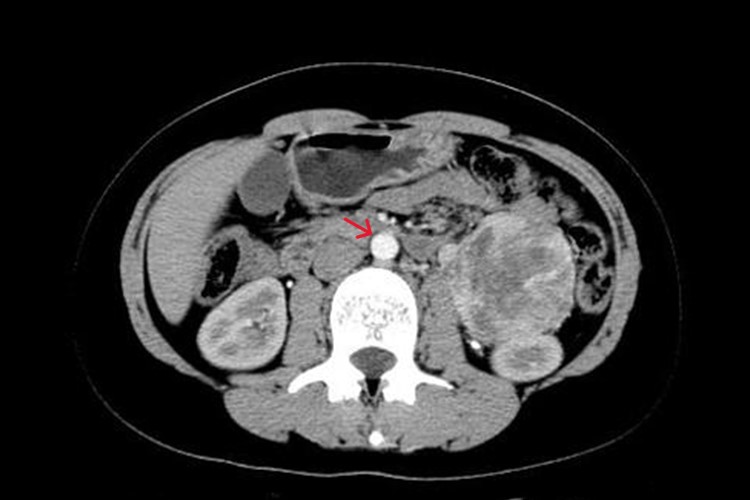

艾滋病合并马尔尼菲篮状菌感染患者的典型症状为出现皮肤损害(脐凹样皮疹、丘疹、结节等)、呼吸道感染(发热、咳嗽、咳痰、胸痛和呼吸困难等)和消化道症状(腹痛、腹胀、腹泻、便血、等),伴有腹腔及腹膜后区广泛的淋巴结肿大。